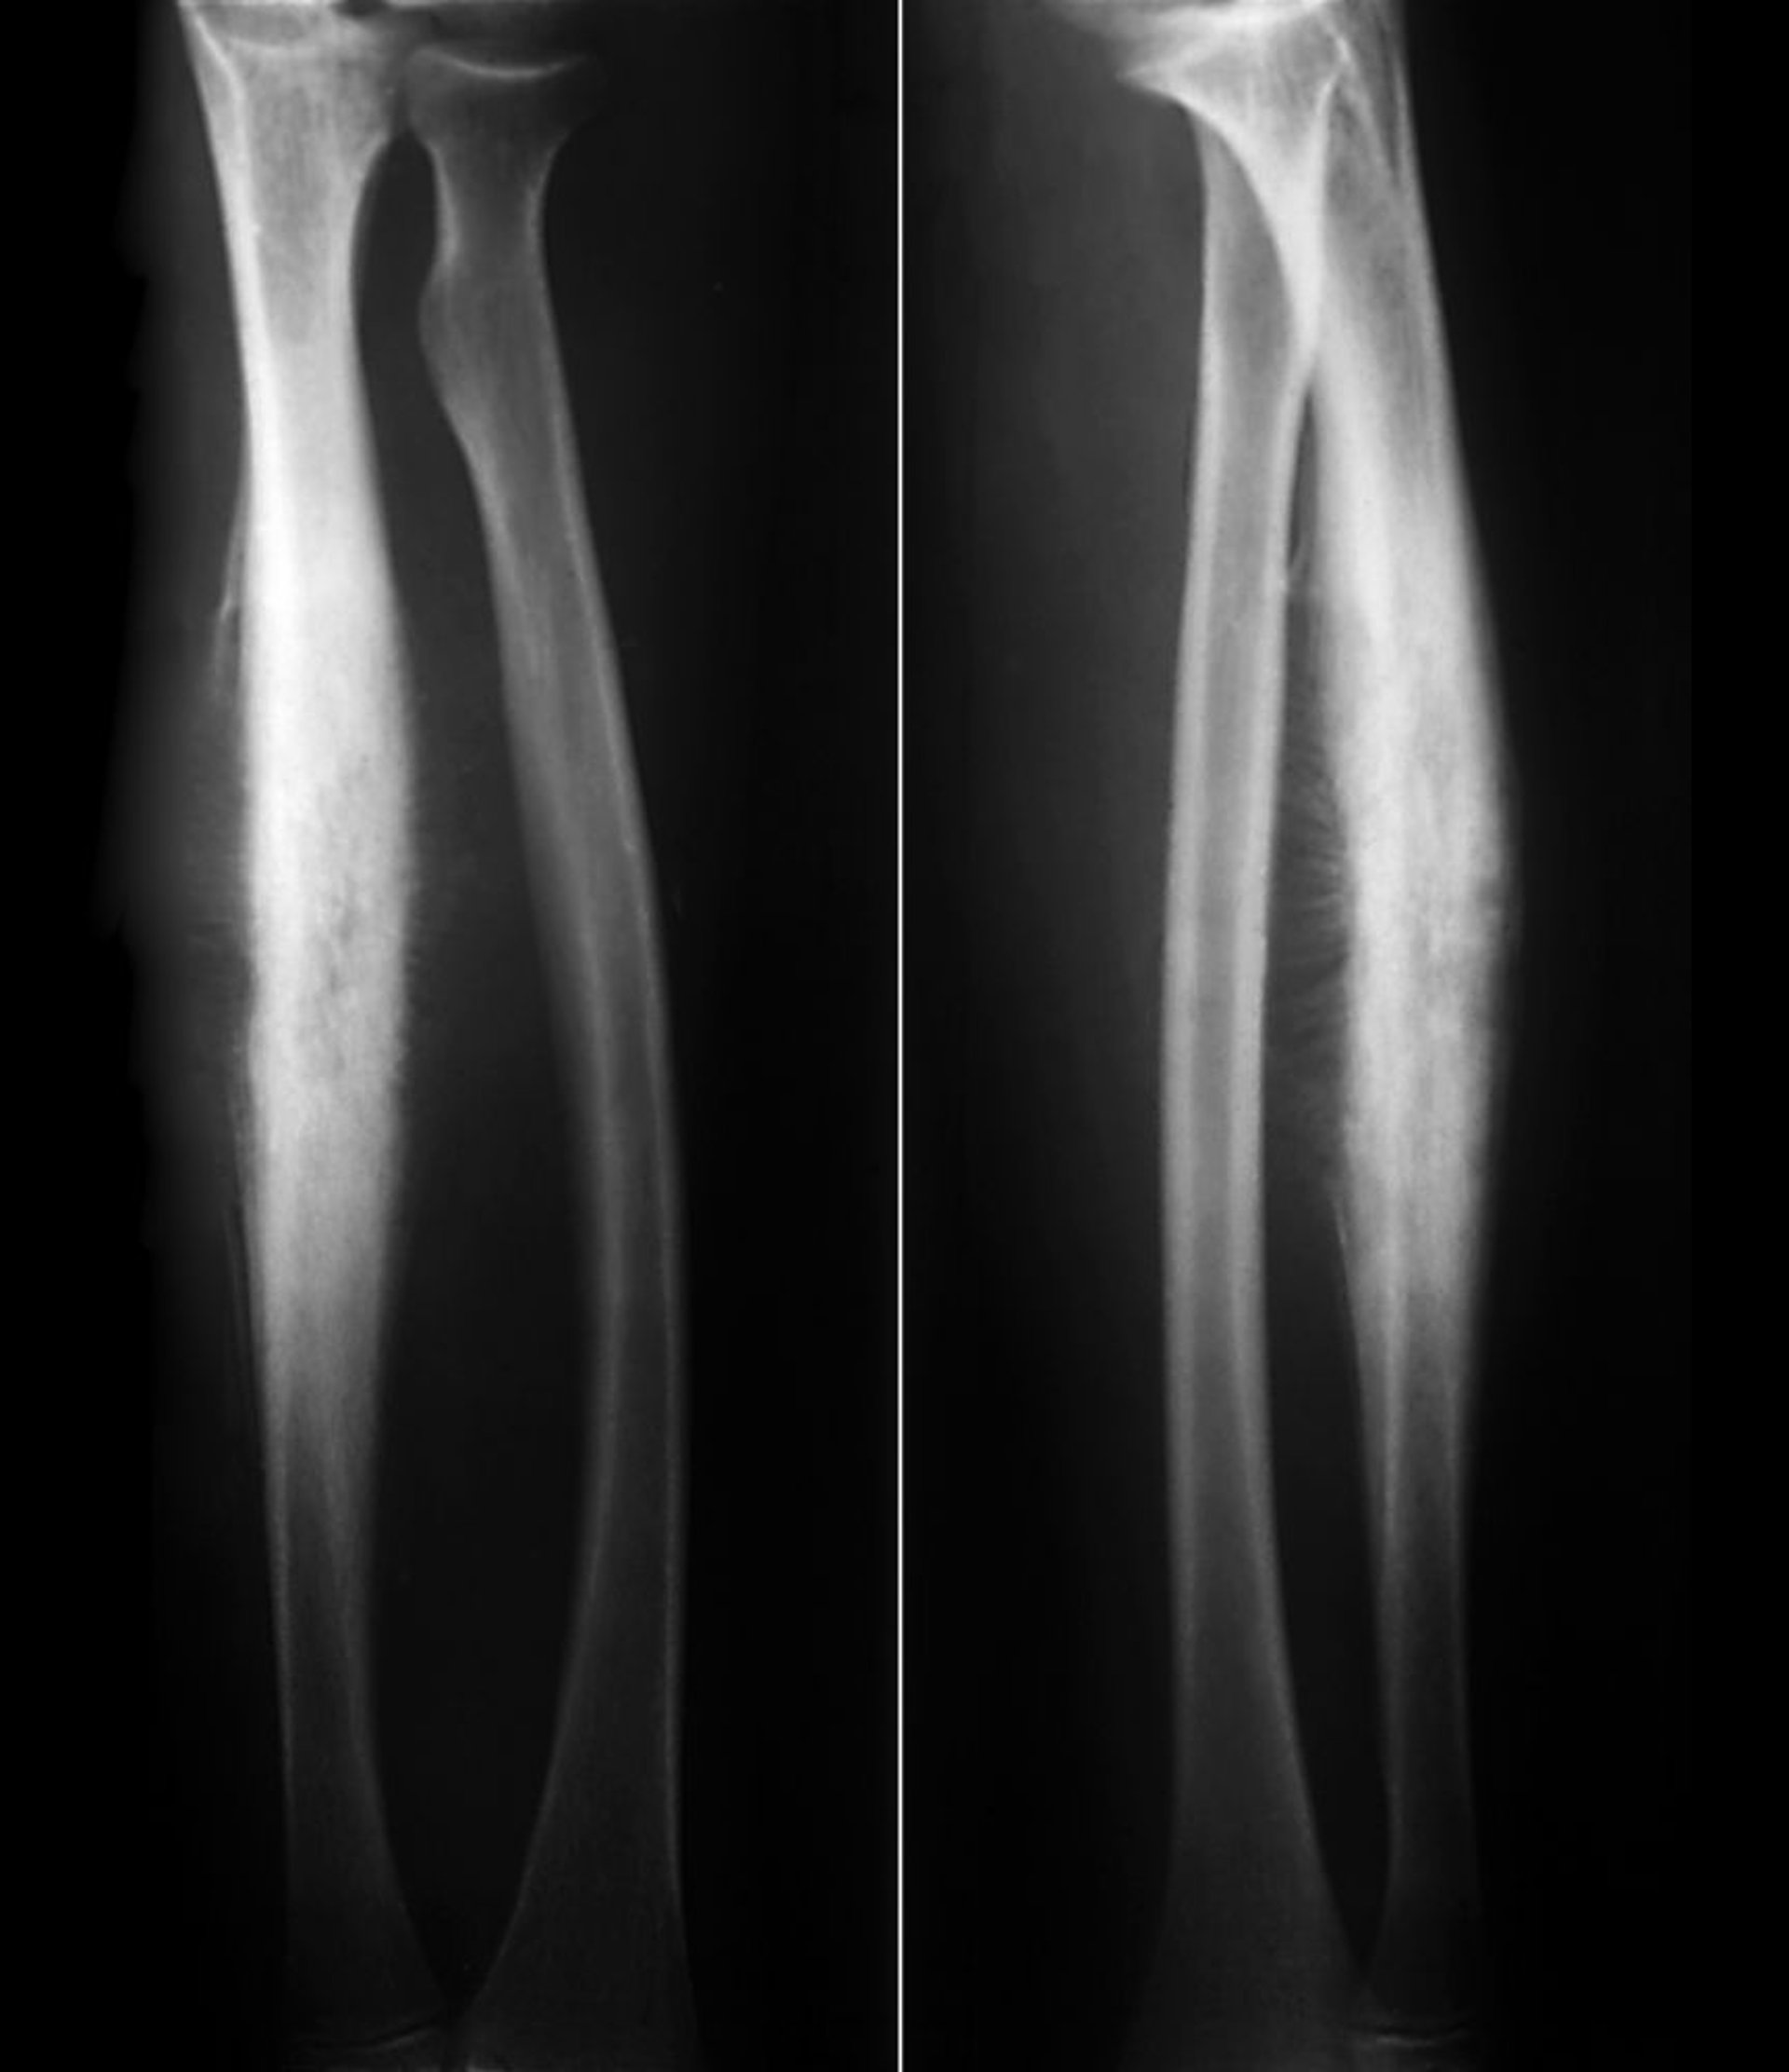

Саркома Юїнга променевої кістки

This Ewing sarcoma of the radial shaft shows subperiosteal reactive new bone formation in a classic "sunburst" periosteal reaction along with lytic destruction of cortical bone.